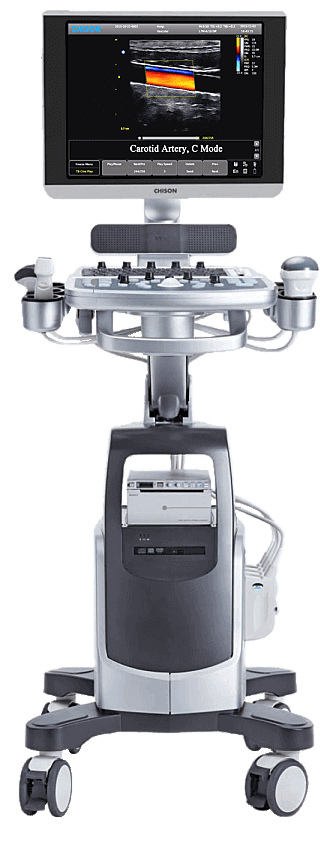

Para empezar, el Ecógrafo Chison QBit-7 mejora la flexibilidad y el flujo de trabajo a un nuevo nivel. Adiciona funciones como el doppler continuo, CW, imágenes tisulares TDI, calculos automaticos IMT.

El Ecógrafo Chison QBit 7 mejora sus procesadores de transmisión y recepción de señal, como resultado, lo llevan a tener una mayor sensibilidad y una detección de eco más precisa.

Además, el Ecógrafo Chison QBit 7 está equipado con una amplia gama de transductores que adoptan tecnologías innovadoras.

Por lo tanto, este modelo promete una experiencia de diagnóstico confiable y como resultado, un rendimiento de alta calidad en todas las aplicaciones.

En conclusión, el sistema de ultrasonido de ultra movilidad Mobility QBit 7 4D cuenta con una tecnología armónica innovadora que utiliza diferentes métodos de transmisión y recepción para pacientes de diferentes tamaños corporales, por lo que maximiza la resolución sin perder la penetración. Por consiguiente, es mejor que el THI tradicional y finalmente las armónicas por fases que mejoran la penetración.

Catálogo Chison QBit 7